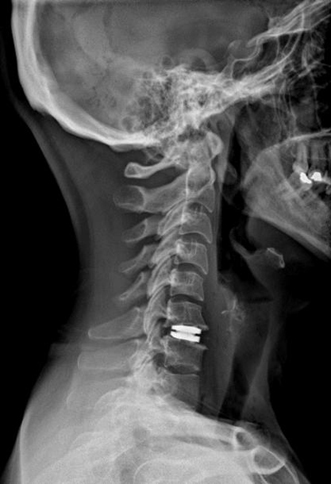

Boyun fıtığının cerrahi tedavisinde amaç, sinir kökünün üzerinde oluşan mekanik basıyı kaldırmak ve sinir kökünü rahatlatmak. Söz konusu bu bası erken dönemde kaldırıldığında sinir dokusu içerisinde daha ileri dönemlerde ortaya çıkabilecek olası kronik ve hatta kalıcı olabilecek değişikliklerin de önüne geçilmiş oluyor. Tedavi geciktiğinde ise -hasta en sonunda ameliyat olsa dahi- bu gecikmeden kaynaklı sinirde oluşan hasar nedeniyle, hastanın ameliyattan faydalanamaması söz konusu. Bu nedenle mutlaka her hasta için en doğru tedavinin ne olacağına, ne zaman ve nasıl yapılacağına karar vermek hayati önem taşıyor. Cerrahi tedavide, boynun ön veya arka tarafından yapılabilen yaklaşımlar var. Arka taraftan yapılan ameliyatlar sinir dokusunun çıktığı kanalın mikrocerrahi tekniklerle genişletilerek sinir üzerinde boyun fıtığından oluşan baskının indirekt yolla giderilmesine dayanıyor. Boynun ön tarafından uygulanan klasik cerrahide ise, iki omurga arasındaki disk tamamen çıkarılıyor ve fıtıklaşmış kısma ulaşılarak sinir rahatlatılıyor. Taşan bölüm temizlendikten sonra iki omurga arasında oluşan boşluğu doldurmak için hastanın kendi vücudunun başka bir yerinden alınan bir kemik parçası (genellikle kalçadan) veya plastik/metal kafesler kullanılıyor. Sonrasında buradaki iki omurganın birbirine tam olarak kaynaması (füzyon) için 2-3 ay beklenmesi gerekiyor. Bu tip bir ameliyat sonrasında boynun hareket kabiliyeti ameliyat edilen her bir seviye için 10-20 derece arasında azalıyor. Bu kayıp, günlük hayatta genelde bir sıkıntı yaratmasa da zaman içinde, ameliyat edilen mesafenin bir üst ile bir alt seviyesinde artan yüklenme ve esnemeye bağlı olarak boyun fıtığı oluşma riskini artırıyor. Bunun tıbbi adı “komşu segment hastalığı.” Bu risk tek seviyede yapılan klasik füzyon ameliyatlarından sonraki her yaşam yılı için %2,9. Birden çok seviyde yapılan füzyon bu yıllık riski daha da artırıyor. Yani her ne kadar başarılı olursa olsun yapılacak servikal füzyon ameliyatı sonrasında er ya da geç ikinci bir ameliyat olma olasılığı yüksek.

Günümüzde boyun fıtığı cerrahisinde hem erken dönemde hareket kabiliyetinin kısıtlanmadan en doğal şekliyle korunması hem de söz ettiğimiz “komşu segment hastalığı”nın önlenmesi açısından tercih edilen yöntem servikal disk protezleri. Bu protezler vücudun kabul ettiği, herhangi bir alerjik reaksiyon yaratmayan özel plastik ve seramik alaşımlar ile titanyum gibi hafif ve çok dayanıklı malzemelerden üretiliyor.

Ameliyat ne kadar sürüyor?